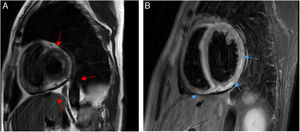

A woman presented with distributive shock, severe septic cardiomyopathy, and encephalopathy. She had sustained a dog bite several days prior. Capnocytophaga canimorsus was isolated from blood cultures. Coronary computed tomography angiography of the lower limbs revealed the presence of vascular involvement. Cardiac magnetic resonance imaging showed ventricular dilation and functional loss, with subepicardial edema (Fig. 1A, SAX T2MAp BH sequence, red arrow) and late gadolinium enhancement (Fig. 1B, SAX TIR BH sequence, blue arrow), consistent with myocarditis. A biopsy of the dermal lesions was performed (Fig. 2, hemorrhagic extravasation [black arrow]; leukocytoclastic vasculitis infiltration [yellow arrow]; and fibrinoid necrosis [white arrow]). The initial lesions are shown (Fig. 3A, purpura fulminans type) and weeks later, prior to distal amputation (Fig. 3B, established necrotic lesions, yellow arrow).